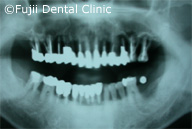

| 術後パノラマ写真および口腔内写真 |

ヘビースモーカーであったために、禁煙してもらい、歯のクリーニングやブラッシング指導後、およそ2年間かけて左上犬歯と左下第一小臼歯以外すべての歯を抜歯し、インプラントの埋入手術を行いました。左右上顎臼歯部はサイナスリフトなどを併用し、インプラントによる咬合の再構築を試みました。